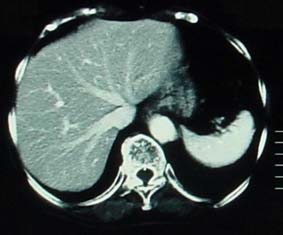

CT

CTは、放射線を用いて、画像をコンピューター処理することにより身体の断面像を得ることができます。脳の検査として非常に有用です。 脳、肺、腹部臓器、骨盤内臓器の観察に使われる。動いているものの観察には向きません。